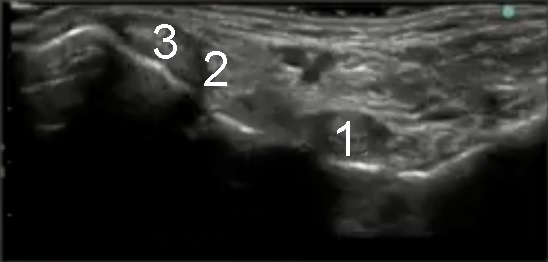

Foot & Ankle Flexor Hallucis Longus Normal Image

1. Flexor Hallucis Longus

2. Flexor Digitorum Longus

3. Posterior Tibialis Tendon